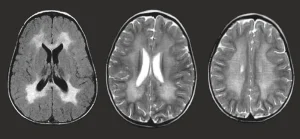

Metachromatic leukodystrophy is a rare inherited metabolic disorder that affects the nervous system. It is caused by a deficiency of an enzyme needed to break down certain fatty substances in the body. As these substances accumulate, they damage the myelin sheath, the protective covering around nerve fibers in the brain, spinal cord, and peripheral nerves.

Metachromatic leukodystrophy is caused by genetic mutations that lead to a deficiency of a specific enzyme responsible for breaking down sulfatides, a type of fatty substance.

Accumulation of sulfatides leads to progressive nerve damage